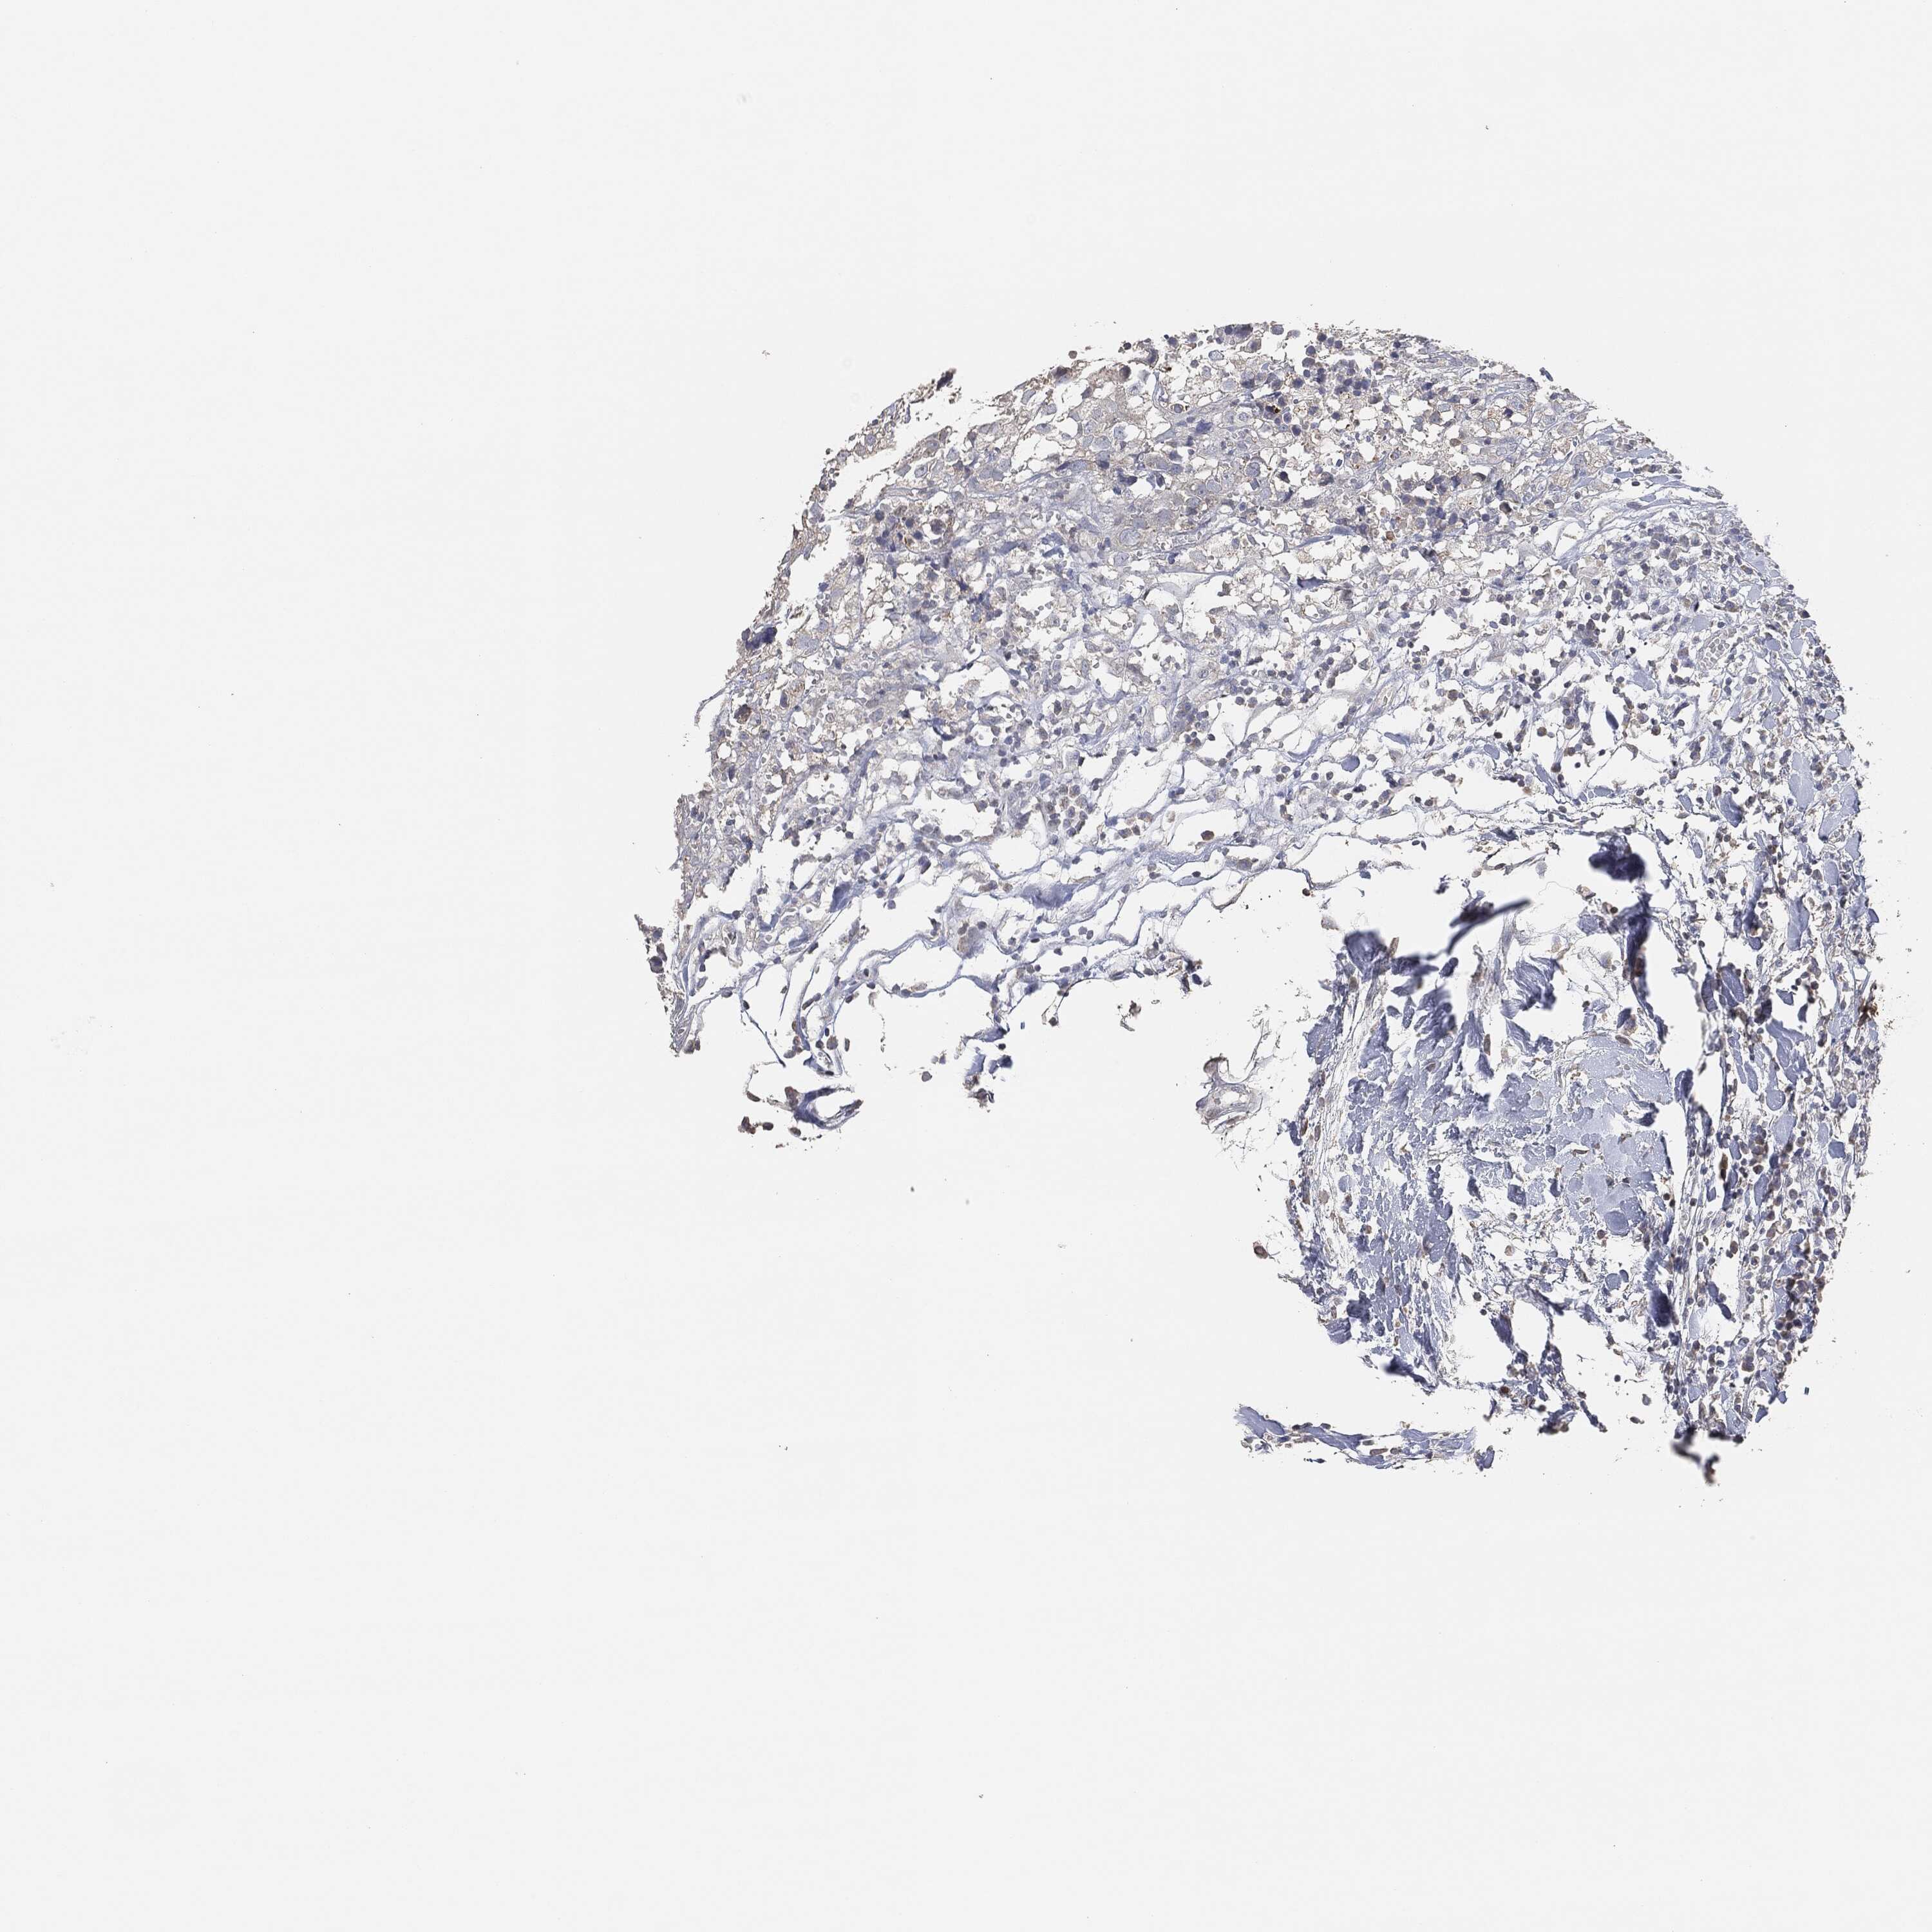

BRCA TCGA BRCA VALIDATION PROTEIN EXPRESSION

ANTIBODIES

AND

VALIDATION